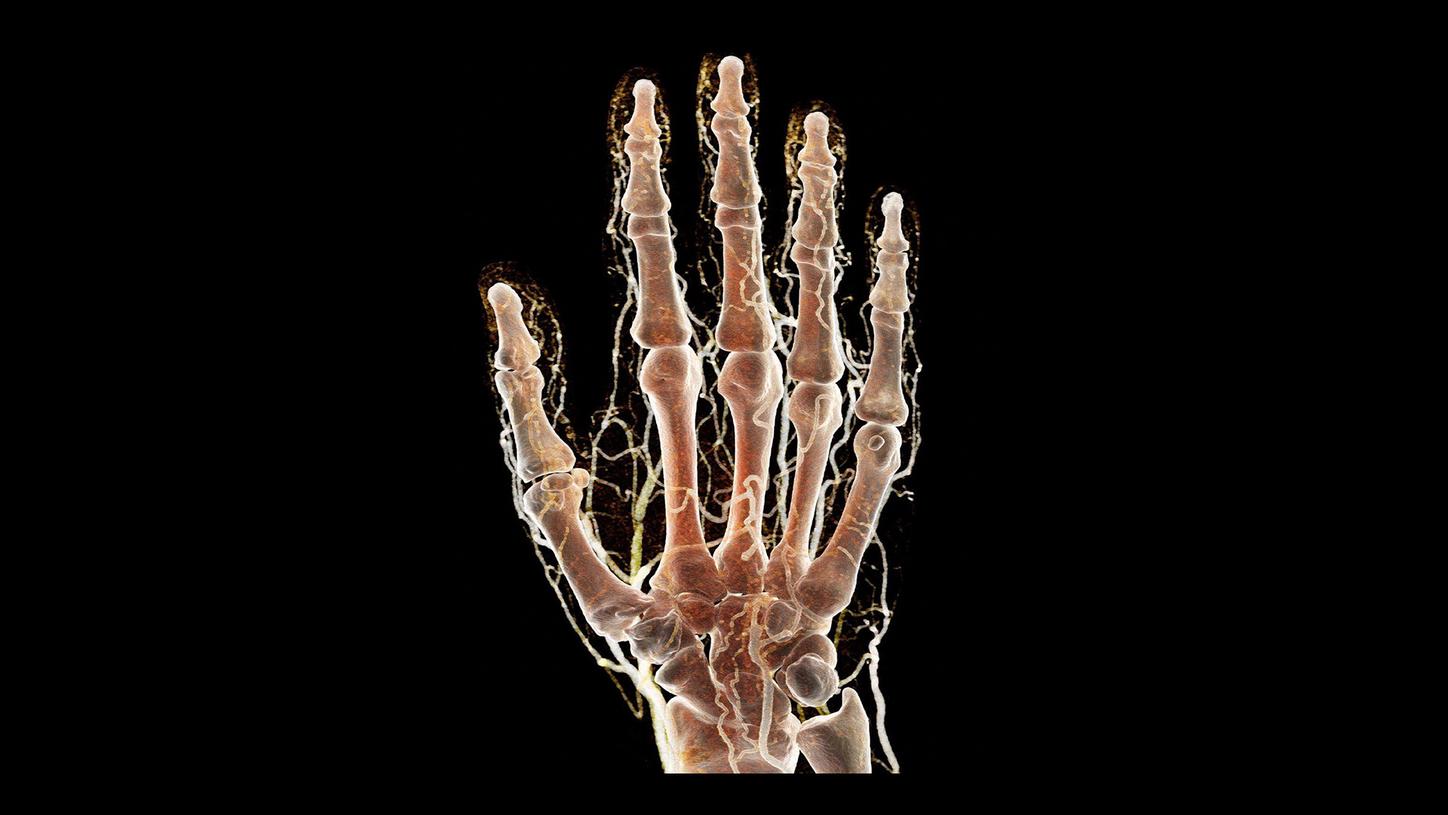

QuantaMax, the first photon-counting detector, overcomes the limitations of conventional CT detectors by providing data at high spatial resolution, without electronic noise and with improved contrast-to-noise ratio.

Vectron X-ray tube enables high image quality, even for patients with high BMI. The microfocal spot (0.4 mm x 0.5 mm) allows to utilize the high spatial resolution of the QuantaMax detectors.